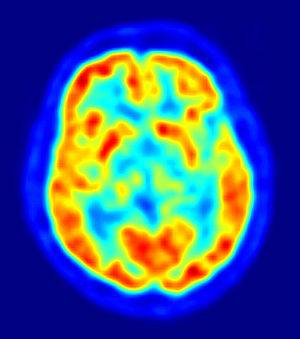

No mathematical formula for "thoughts and emotions", but there are tools for measuring brain activity like PET, MRI, EEG, MEG, etc. This will only show where the activities are in the brain.

300px-PET-image.jpg

PET scan of the human brain